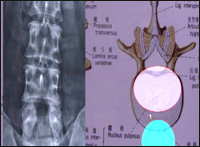

主持人:老百姓通常所说的闪腰与腰椎不稳有关系吗? 田伟:闪腰是腰椎不稳定的一种表现,偶尔出现一次闪腰不一定会造成腰椎不稳定,但是如果反复出现闪腰就很容易造成腰椎不稳定。首先来通过一张图了解一下腰椎的结构,正常的腰椎由5节骨头连接起来,图中所示有椎间盘、后方的关节、关节囊、韧带等,韧带连接对腰椎的稳定性起着非常重要的作用,当病人出现了闪腰或反复的闪腰实际上就预示着正常的结构可能受到了损伤,软骨盘是损伤后造成不稳定的重要因素,到医院就诊我们会发现一些异常情况如下图,通过弯腰和伸腰时的X光片可以看到腰椎发生不稳定的阶段椎间的活动度增大,这本身就说明了正常结构有损伤。另外一张图,本来椎体互相之间连接是比较整齐的,但是在异常阶段实际上有一部分向前发生了移动,这也是腰椎不稳定的一种表现。

主持人:来看一位患者的情况。患者:"我的腰疼加剧后上医院按摩,按摩了大约有半年,疼痛越来越厉害,到医院检查后做了第一次手术,医生说是按摩把软骨揉碎了,压迫了神经,手术后5个多月又开始疼,吃药也不管事儿,后来又上积水潭医院看病。" 田伟:一旦出现了腰痛以后一定要找专业医生检查,从结果上看可能是腰痛时本身的软骨盘已经出现了损伤,可能髓核组织并没有跑出来或损伤的裂痕并不是很大,在这种情况下如果做比较剧烈的按摩就会增加损伤的程度,并不是说按摩在任何情况下都不能用,但是在这种情况下并不适合。出现这种情况后患者又进行了手术,手术是一种比较正确的治疗方法,但是手术效果并不好,来看一张图,过去做腰椎脱出手术一般要切除比较多的结构,手术把正常的结构切除得很多,椎间盘也切除了很多,虽然当时神经压迫解除了但是以后又出现严重的腰疼反映了切除这些组织后加上原来的因素就造成了一个腰椎不稳定的结果。 刘波:我们目前还在探讨出现椎间盘突出以后这种状态是否已经出现有腰椎不稳的情况,通过拍片子、症状体位等检查,如果发现已经有腰椎不稳的情况,就要找出不稳定的部位,然后针对不稳定的部位进行融合、固定,如果椎间盘突出并没有出现脊柱不稳的情况,只是髓核压迫神经,手术就应该尽量做得微创,尽量保存韧带、关节的结构,这样既可以解除症状又可以尽量保持相对稳定的结构,就可以避免以后出现腰椎不稳定。